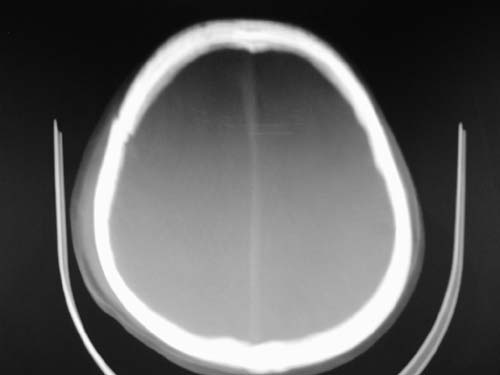

标题: CT17020:是硬膜下的吗?

脑中线内血肿,是硬膜下的吗?

脑中线内血肿——硬膜下血肿。

脑中线内血肿——硬膜下血肿。我们一般认为中线即可是硬膜下,也可是蛛网膜下腔的。边缘锐利,张力高的考虑硬膜下的,边缘模糊的,考虑下腔的。如果有老师有肯定的答案,麻烦下给我发个短信

硬膜下血肿,有颅骨骨折

支持镰旁硬膜下血肿,颅骨骨折,头皮损伤.

这个病人年龄不小吧,右侧脑沟不清,中线结构稍有左移,右侧额颞顶及右镰旁硬膜下血肿,另有蛛血,骨折。

外伤后引起的颅骨骨折、硬膜下血肿、皮下血肿,颅骨骨折引起的矢状窦破裂,形成大脑纵裂内血肿。